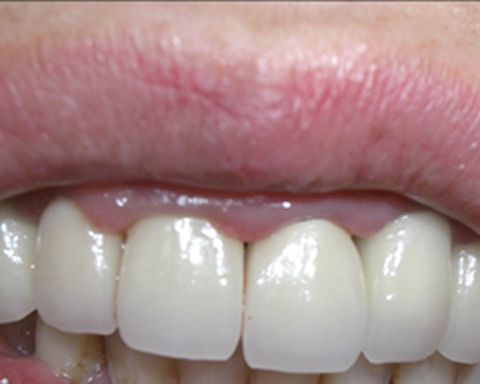

インプラント症例